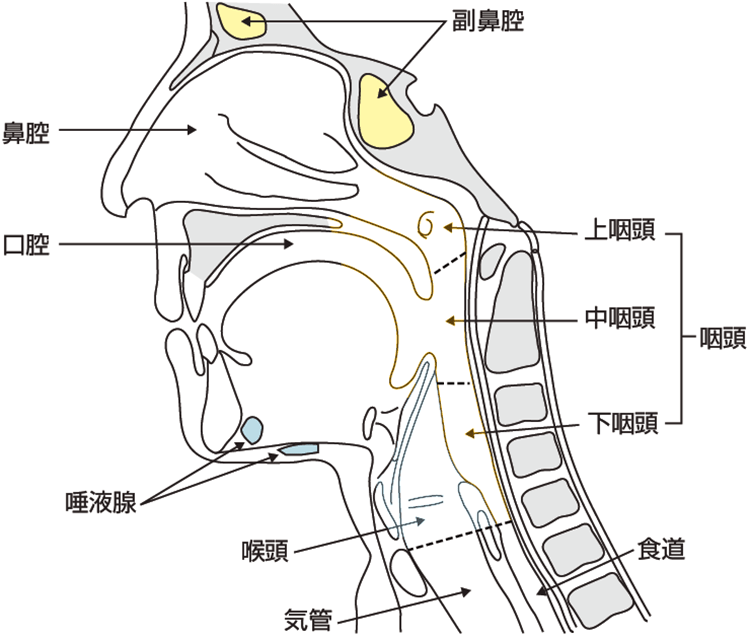

頭頸部癌 Amazon.co.jp: 臨床頭頸部癌学(改訂第2版): 系統的に頭頸部癌をの詳細情報

Amazon.co.jp: 臨床頭頸部癌学(改訂第2版): 系統的に頭頸部癌を。頭頸部がんの治療-頭頸部がん | 病気と治療の検索サイト。頭頸部がん治療 | 藤田医科大学 耳鼻咽喉科・頭頸部外科。「頭頸部癌」垣添 忠生 / 林 隆一定価: ¥ 10000#垣添忠生 #垣添_忠生 #林隆一 #林_隆一 #本 #自然/医療・薬学・健康ところどころラインマーカーが引いてあります。灸法実践マニュアル : 開業鍼灸師のためのガイドbook : 督脈通陽法で治療…。公式】頭頸部外科|湘南鎌倉総合病院。大きな汚れはないですが、使用感はあります。